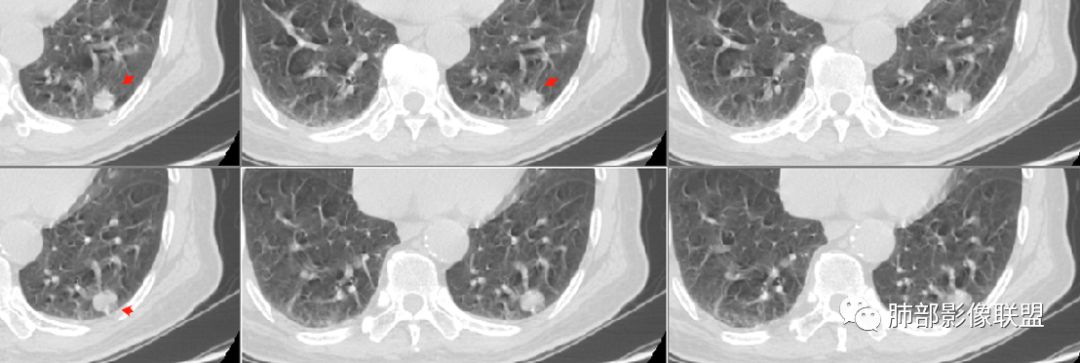

病例2资料

群内讨论

徐天鹏,宁夏海原县人民医院,放射:第二例结节局部膨隆,有血管进入,细支气管截断,考虑腺癌?

明日の路过:第二例,患者病灶在左肺上叶,分叶、空泡、血管供养征,感觉跟书上的恶性肿瘤图片一模一样。考虑恶性肿瘤可能。建议全身筛查后直接切除。

晨: 第二例,患者病灶在左肺上叶,有分叶、空泡、血管供养征,气管截断,考虑恶性肿瘤,腺癌可能。

紫气东来:病例二,结节内空泡,支气管截断,血管进入,考虑恶性。

王开金江津中心医院呼吸科:病例二,左上叶类圆形结节,分叶,毛刺,血管集束证,空泡,考虑腺癌,鉴别结核球。

欣:第二例:界清结节,有分叶,支气管截断,空泡征,腺癌,IAC

高广飞:有分叶,毛刺,空泡,腺癌?

晨读病例二,左肺上叶小结节病灶,有分叶,支气管受阻塞,中断,内可见小泡征,首先考虑恶性病变,腺/鳞癌可能。

波波:第二结节局部膨隆,分叶,空泡,细支气管截断,考虑腺癌。

晨读二:左肺上叶结节,深分叶,支气管堵塞并挤压,内部可见偏心性空泡,考虑恶性,腺癌,早期鳞癌。

大宝儿.蕊:上叶实性结节,边界清,分叶,短毛刺,小泡征,血管集束征,腺癌首先考虑。

南大分析病例2

南边:

支气管截断。

支气管在门口堵塞恶性居多,结核有时也有。

空泡

分叶

血管纠集

毛刺

总体分析,支持恶性。

应当说两例患者影像学表现都具有比较明显恶性征象,中老年男性患者,均都没有呼吸系统临床症状。

病例2肉瘤样癌的病理意见有些出乎预料,也充分说明病变及影像表现的复杂性。病灶小结节支气管截断、空泡、分叶、短毛刺、血管集束征等似乎均符合肺癌的影像特性。肺鳞癌及肉瘤样癌往往范围较小就可以出现坏死,但如果结节太小则很少能够在影像上观察到坏死区或空洞,没有增强扫描图像更是如此。